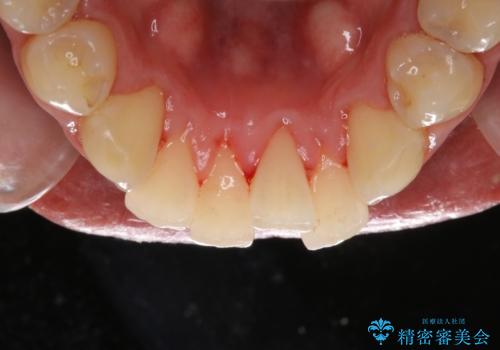

- 結婚式を控えているため、クリーニング希望とのことで来院されました。歯科医院がかなり久しぶりとのことでした。

全体の染め出しを行い、歯科衛生士による専門的自費クリーニング(PMTC)60分コースを行いました。